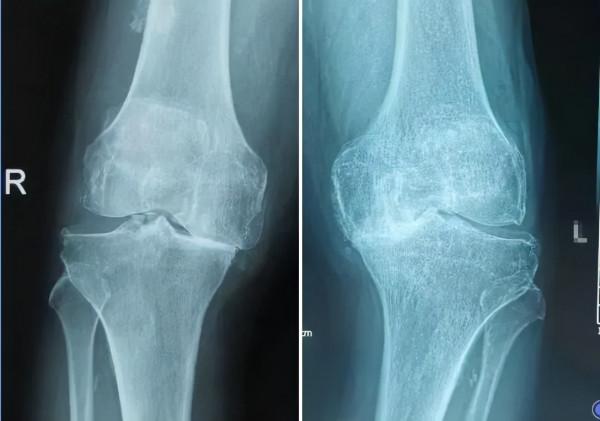

AugustineC. Lee等開展了一項關於太極拳與物理治療運動干預對症狀性膝骨關節炎量-效關係比較的研究。

1.太極拳與物理治療運動干預在改善膝骨關節炎疼痛及功能障礙方面都有效,兩者在量-效關係方面是差不多的。

2.太極拳用於膝骨關節炎康復治療,最小起效時間為2-5周。

3.太極拳用於膝骨關節炎康復治療,膝關節疼痛和功能改善超過20%平均需要2周時間,改善超過50%則需要4-5周時間。